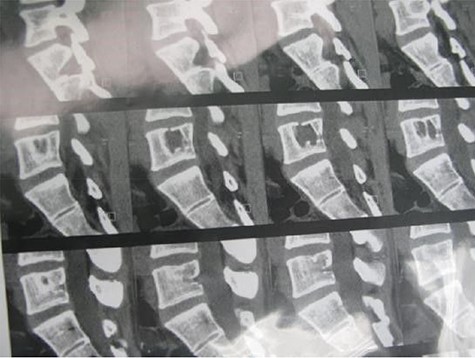

A 24-year-old male presented with acute low back pain with no prior traumatic events. Physical examination was unremarkable except for tenderness over the lower thoracic spine. The laboratory tests including complete blood count, renal function tests, alkaline phosphatase, aspartate aminotransferase, alanine aminotransferase, serum calcium, serum phosphorus and parathyroid hormone were all within normal limits. Initially, the patient was treated conservatively but the pain did not improve. Lumbar X-ray showed mild height loss and fracture of the superior endplate of T12 vertebra (Fig. 1). Computed tomography (CT) showed a multi-lobulated osteolytic lesion within the T12 body with extension to the right pedicle and transverse process (Fig. 2). Magnetic resonance imaging (MRI) revealed a well-defined lesion with low signal intensity on T1 and high signal intensity on T2 weighted images (Fig. 3). The bone scan showed a cold spot at the site of the lesion. The patient underwent surgery and excisional biopsy through the posterior approach. A large clear fluid-filled cavity was curetted and the cavity was filled with an autologous bone graft from iliac crest. Posterior spinal fusion was performed with instrumentation with pedicle screws from T10 to L2 and a mixture of autologous bone graft and allograft was used to achieve better fusion (Fig. 4). Pathology report confirmed the diagnosis of SBC and the patient received no further treatment (Fig. 5). The patient had no recurrence in 10-year follow up.

A 26-year-old male presented with pain over the lower lumbar area. Physical examination and laboratory tests were unremarkable with no neurologic deficit. X-ray and CT scans showed a lytic lesion with a sclerotic border in the right half of the body of the L5 vertebra (Figs 6 and 7). MRI showed a well-defined low signal lesion in T1 weighted images and high signal lesion in T2 weighted images (Fig. 8). The bone scan was negative. The patient underwent surgery and the lesion was extracted through the right pedicle and the remaining cavity was filled with an autologous bone graft from the iliac crest and right-side posterior fusion was done from L4 to L5 (Fig. 9). The pathology report was consistent with SBC. The patient had no recurrence seven years after surgery.